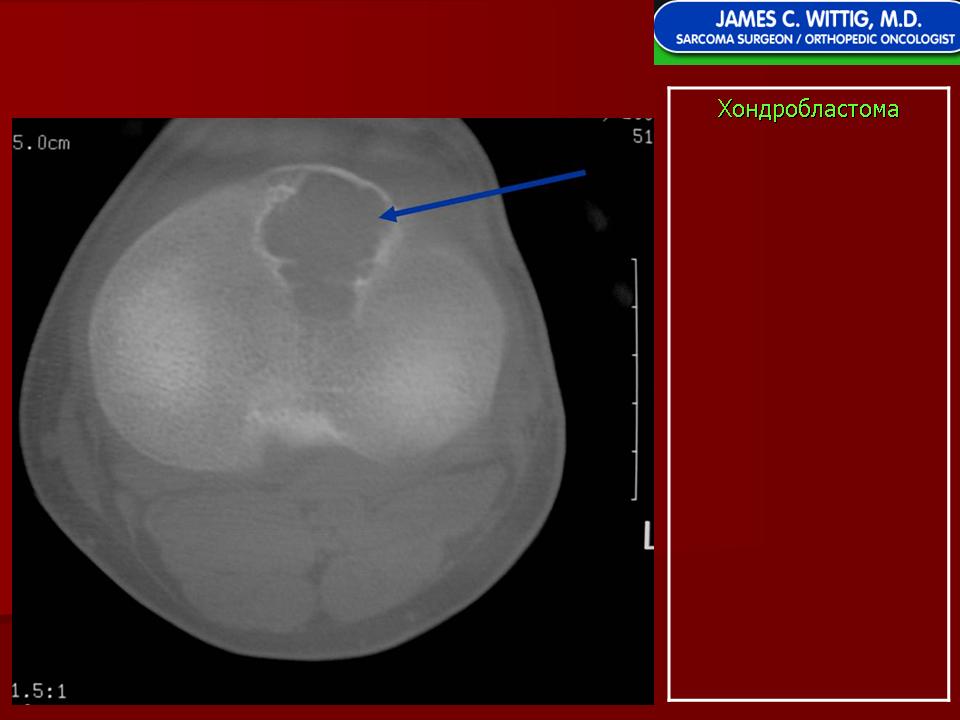

Хондробластома — это редкая доброкачественная опухоль, локализующаяся, главным образом, в эпифизе и отличающаяся своеобразным клеточным составом. Ткань новообразования представлена овальными, округлыми и веретеновидными клетками, напоминающими незрелые хондроциты (хондробласты). Зрелый гиалиновый хрящ определяется лишь в некоторых опухолях. Возраст больных варьирует. Мужчины поражаются в два раза чаше женщин. Пациенты предъявляют жалобы на боли в течение нескольких месяцев или лет, у некоторых больных определяются внутрисуставной выпот, припухлость и ограничение движений. Наиболее типичная локализация опухоли — проксимальные эпифизы плечевой и большеберцовой костей, а также дистальный эпифиз бедренной кости. У 20 % больных опухоль развивается в плоских или коротких трубчатых костях, преимущественно в пяточной и таранной. Изредка поражаются кости лицевого черепа, в том числе височная. В большинстве случаев новообразование выходит за пределы эпифиза и распространяется на метафиз. На фоне остеолиза обнаруживаются рассеянные участки обызвествления в виде пунктирных линий, а также разреженный трабекулярный рисунок. Хондробластома, как правило, не выходит за пределы кости, но изредка проникает в полость сустава. В процессе роста опухоли иногда возникает вторичная аневризматическая костная киста.

Рентгенологически хондробластома представляет собой сравнительно большой (2-4 см) очаг округлой формы, четко отграниченный от окружающей кости склеротической каймой. На фоне очага в большинстве случаев, но не обязательно определяются плотные включения, напоминающие хлопья ваты.

Рентгенологическая картина. Хондробластома выглядит как небольшой, от 3 до 6 см литический очаг, центрально или эксцентрично расположенный, с четкими контурами, занимающий около половины площади эпифизарной зоны. Хондробластома плоских костей и мелких трубчатых костей больших размеров, может сопровождаться припухлостью мягких тканей, вздутием кости и периостальной реакцией. Распространение процесса на метафизарную зону встречается часто.